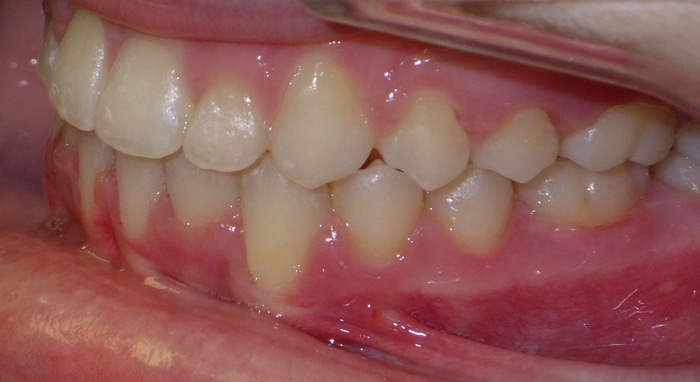

EMILY’S SMILE JOURNEY

Emily began with us as a Phase I patient and we just recently debanded her from Phase II. These progression photos show you that starting early allows us to not just straighten the teeth, but also change the patient’s jaw shape. Emily was a dedicated patient and did great with treatment. Her results speak volumes! We were able to correct her severe underbite and Class III skeletal imbalance without needing jaw surgery.